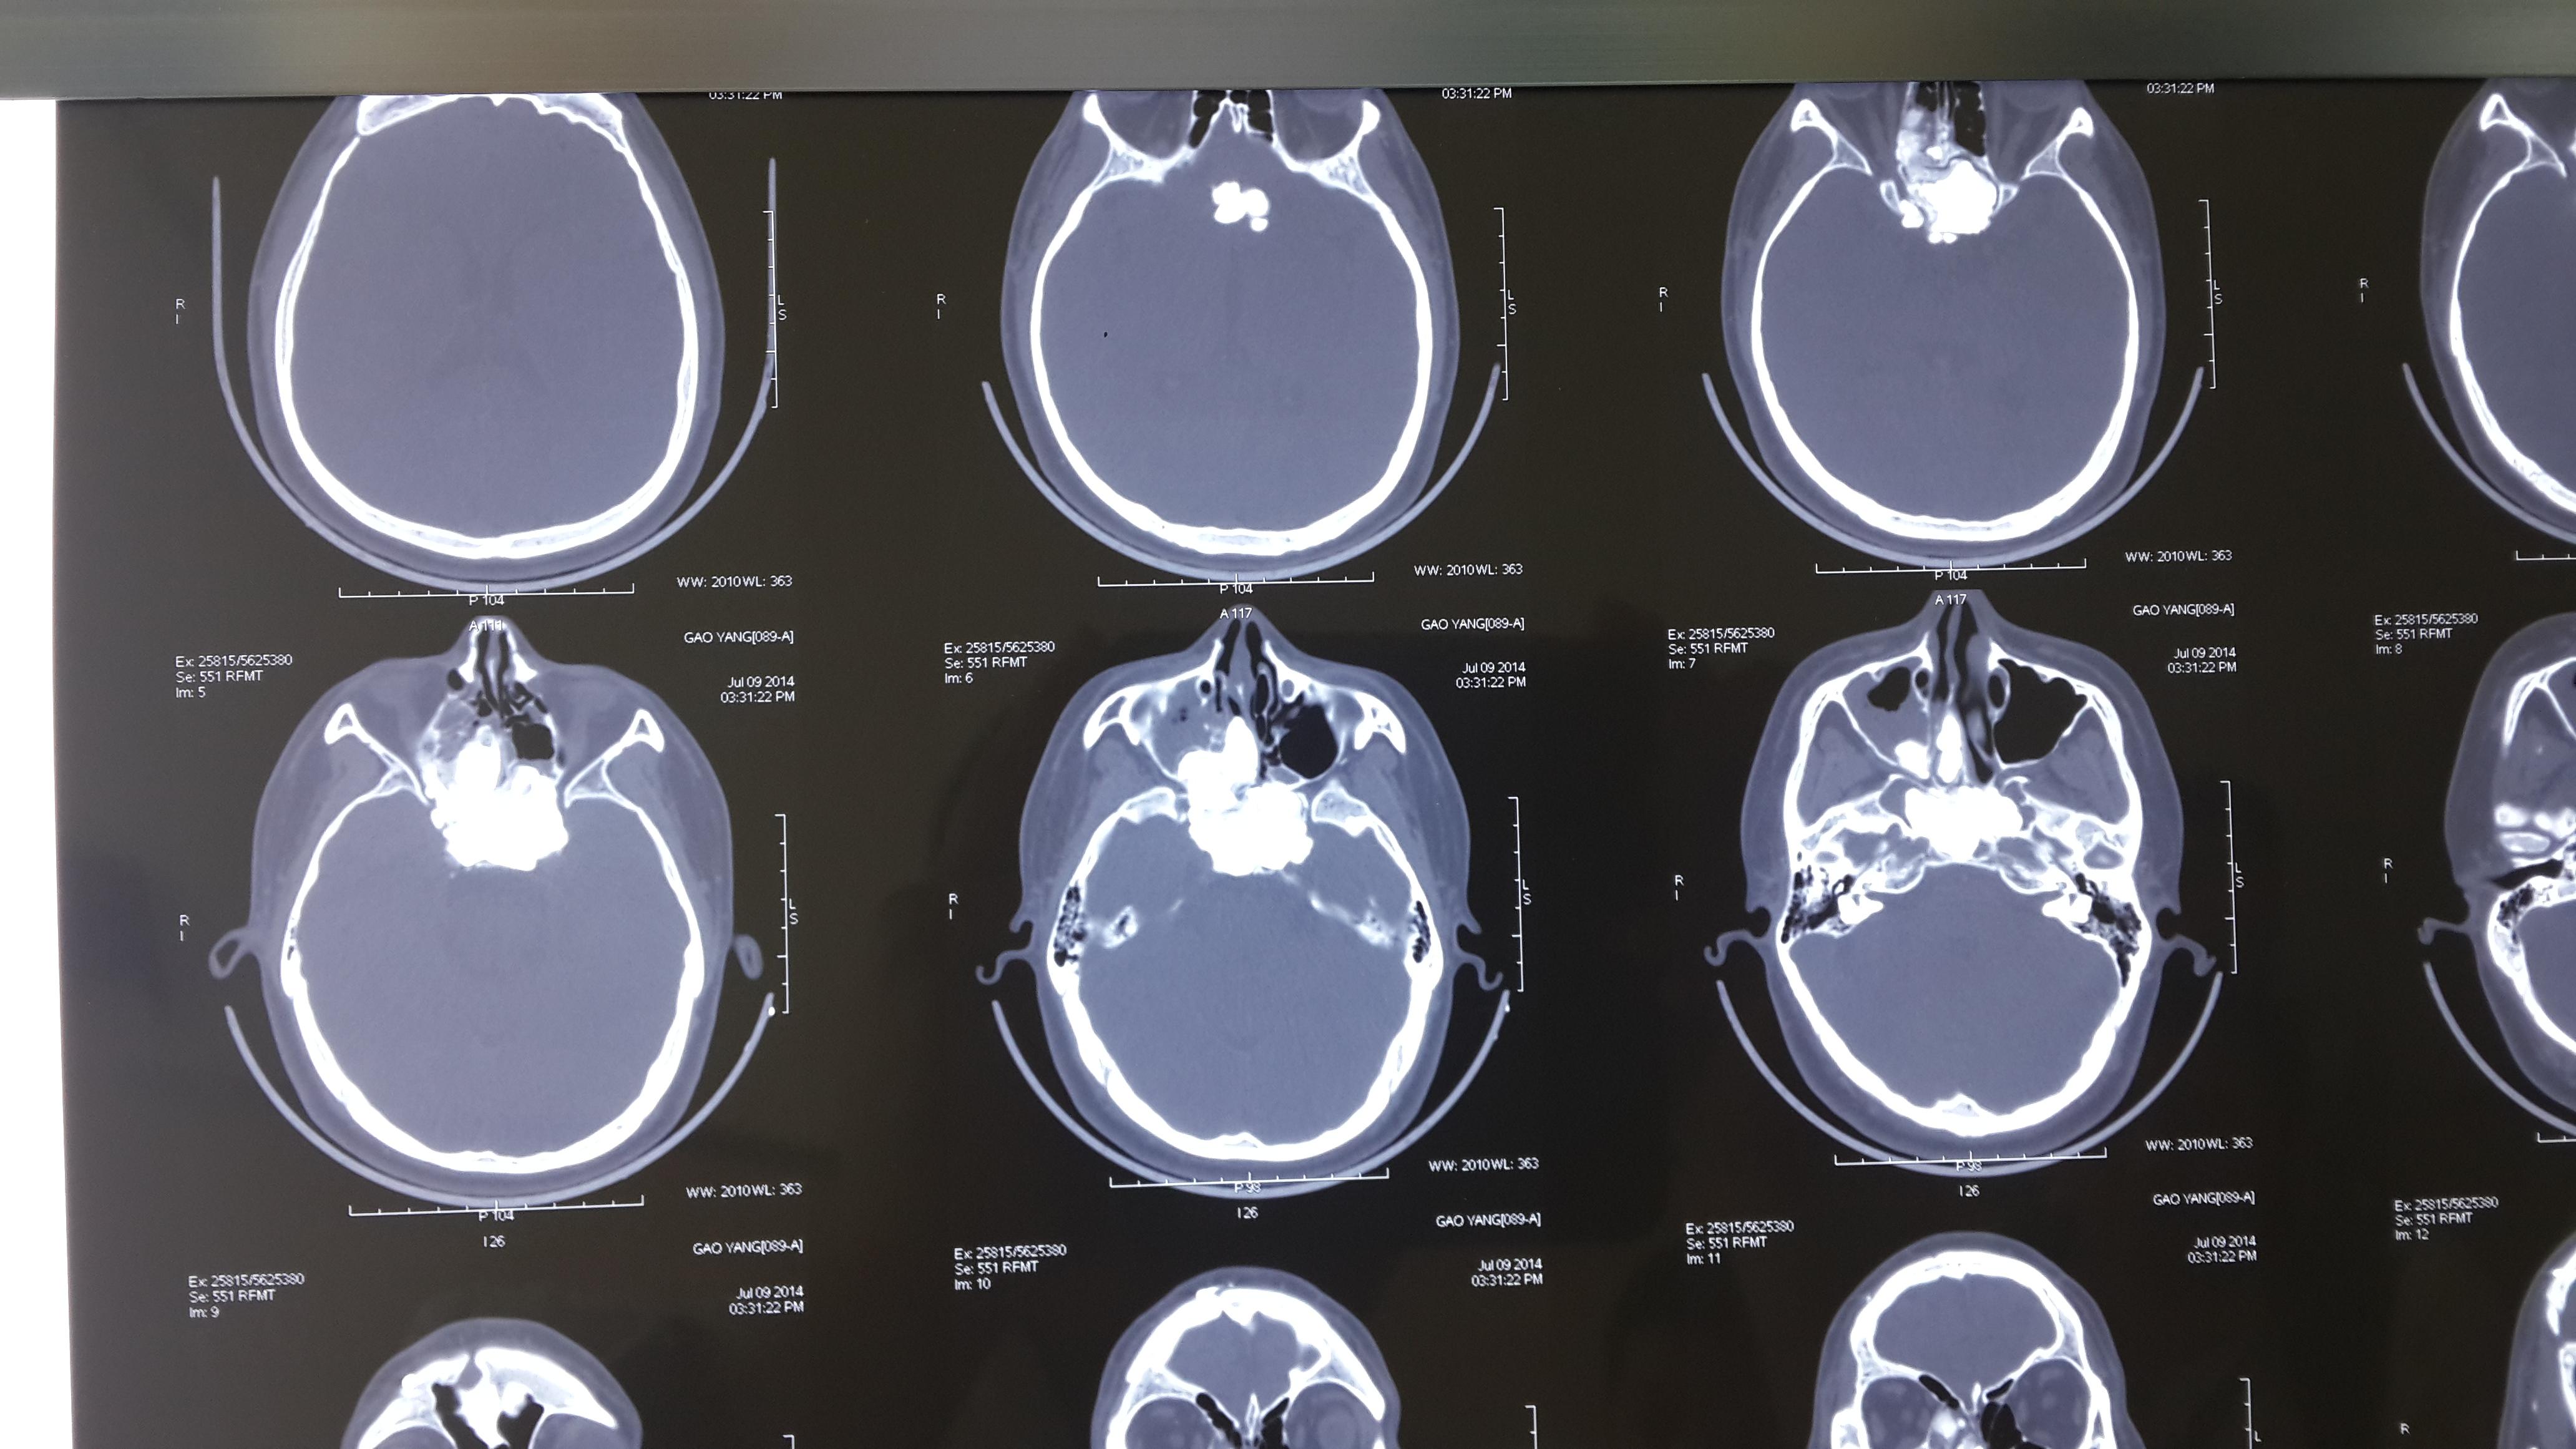

复查ct可见脑室出血逐渐减少,中

2019年9月18日我院256排ct加增强 2019年9月18日我院mr颅底平扫